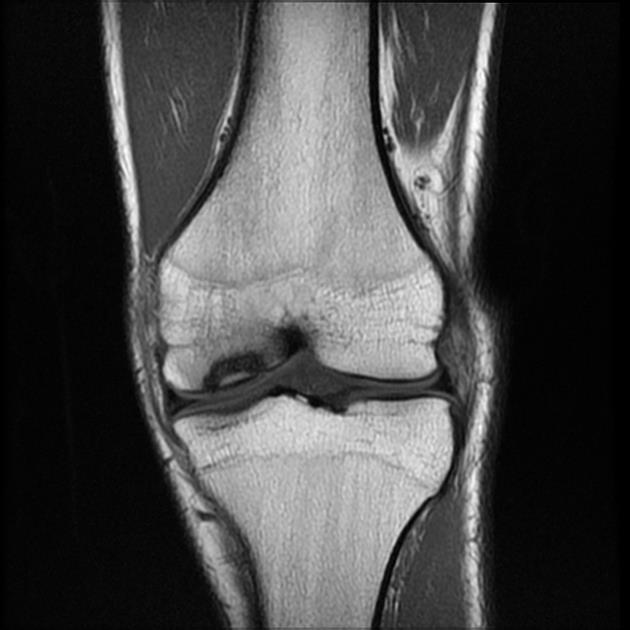

Специфическим признаком РВС является остеохондрит Вегенера - поражение длинных трубчатых костей на границе эпифиза и диафиза, обусловленное нарушением образования кальция и торможением развития остеобластов. Выделяют три степени остеохондрита. Характерными для РВС являются II и III степени. Наряду с остеохондритом, у детей грудного возраста часто обнаруживаются периостальные наложения при рождении и в первые месяцы жизни, поражающие длинные трубчатые кости и череп. Остеохондриты и периоститы обнаруживаются симметрично в нескольких костях. Возможно развитие гумм в метафизах и диафизах, вызывающих переломы и псевдопаралич Парро. При этом наблюдается локальная болезненность и отек в зоне поражения. Конечность выглядит парализованной, но чувствительность и движения пальцев сохранены. Возможно развитие фалангитов или дактилитов с деструктивными гуммозными и периостальными изменениями [1, 5, 29]. Данные поражения протекают безболезненно и не образуют свищей. По нашим данным, самым частым признаком РВС на сегодня является поражение костей. У 43 (56,6%) больных был диагностирован остеохондрит II степени, а у 3 (3,9%) - III (рис. 4, а, б). Рисунок 4. (а, б). Остеохондрит II степени у новорожденного с РВС. Часто выявлялись периоститы трубчатых костей, сочетающиеся с остеохондритами II степени (рис. 5, а, б). Рисунок 5. Сифилитический диффузный остиомиелит трубчатых костей (внутриметадиафизарный перелом проксимального отдела плечевой кости) до проведения специфической терапии (а) и после лечения (б). Псевдопаралич Парро наблюдался у 1 ребенка (рис. 6). Рисунок 6. Псевдопаралич Парро левой руки у ребенка 1,5 мес с РВС. Также у 1 ребенка, поступившего в возрасте 2,5 мес, диагностирован остеохондрит II степени, периостит, эпифизарная гумма фаланги II пальца кисти и фалангит, возникающий то на одном, то на другом пальце.

Особенно часто поражается у плода костная система, где уже к 6-7-му месяцу внутриутробного развития на границе кости и хряща трубчатых костей имеются изменения по типу остеохондрита. В сомнительных случаях рентгенологическое выявление остеохондрита у мертворожденных плодов является патогномоничным симптомом раннего врожденного сифилиса.

Наиболее типичной формой поражения костной системы при раннем врожденном сифилисе является сифилитический остеохондрит Вегнера, который развивается с 5-го месяца внутриутробного развития. В настоящее время остеохондрит Вегнера I—II степени является наиболее частым активным проявлением раннего врожденного сифилиса. Сущность остеохондрита сводится к нарушению процесса окостенения на границе между хрящом эпифиза и диафизом длинных трубчатых костей, чаще — верхних конечностей. Различают три степени остеохондрита. Первые две определяются только рентгенологически. Остеохондрит III степени проявляется клинически в виде псевдопаралича Парро — отсутствия движений конечности при сохранении нервной проводимости. Для диагностики остеохондрита необходимо делать две рентгенограммы: одну— обоих предплечий с дистальным концом плечевой кости, вторую — обеих голеней с дистальным концом бедренной кости. Рентгенологическое обследование следует производить в первые 3 месяца жизни ребенка, так как в более поздние сроки явления остеохондрита могут самопроизвольно разрешиться.